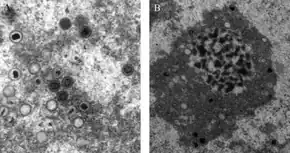

Transmission electron microscope (TEM) image of cytomegalovirus (CMV) virions that were present in a (unknown) tissue sample.

a,b) Clearly defined and non-deformed human cytomegalovirus particles b) types of background texture and deformed particles in cell nucleus

HCMV replicates within infected endothelial cells[19] at a slow rate, taking about 5 days in cell culture.[20] Like other herpesviruses, HCMV expresses genes in a temporally controlled manner.[21][22] Immediate early genes (0–4 hours after infection) are involved in the regulation of transcription, followed by early genes (4–48 hours after infection) which are involved in viral DNA replication and further transcriptional regulation.[21] Late genes are expressed during the remainder of infection up to viral egress and typically code for structural proteins. While HCMV encodes for its own functional DNA polymerase, the virus makes use of the host RNA polymerase for the transcription of all of its genes.[23]